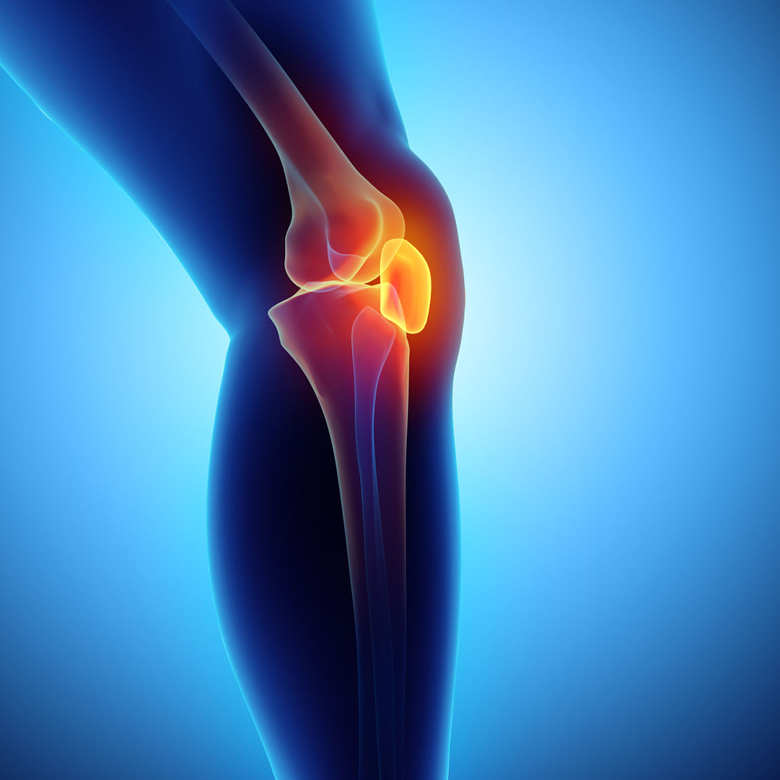

Rheumatic diseases are a group of auto-immune connective disuse disorders. This treatment helps at reducing inflammation and symptoms like pain, swelling, etc,

Ayurananda swedna theraphy transformed my life! My cronic joint pain diminished quickly , and i felt healing like never before.Highly recommend their treatments!